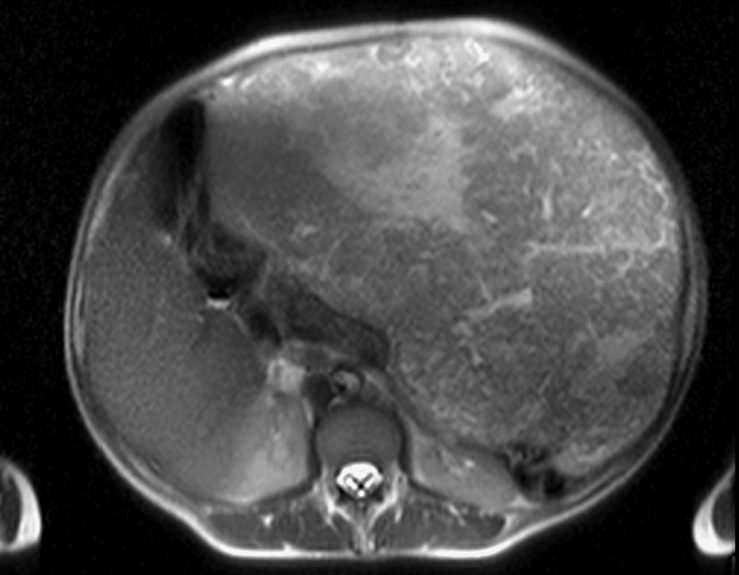

По данным компьютерной томографии (КТ) брюшной полости определялось массивное образование размерами 54×34×22 см, относительно однородной структуры. Опухоль смещала левый купол диафрагмы с левым легким вверх с уменьшением его объема наполовину. Петли кишечника, печень, аорта были смещены вправо. При ангиографии кровоснабжение опухоли осуществлялось за счет желудочно-сальниковых сосудов (рис. 1, 2).

Рис. 1. Гастроинтестинальная стромальная опухоль большого сальника. Петли кишечника, печень смещены вправо.